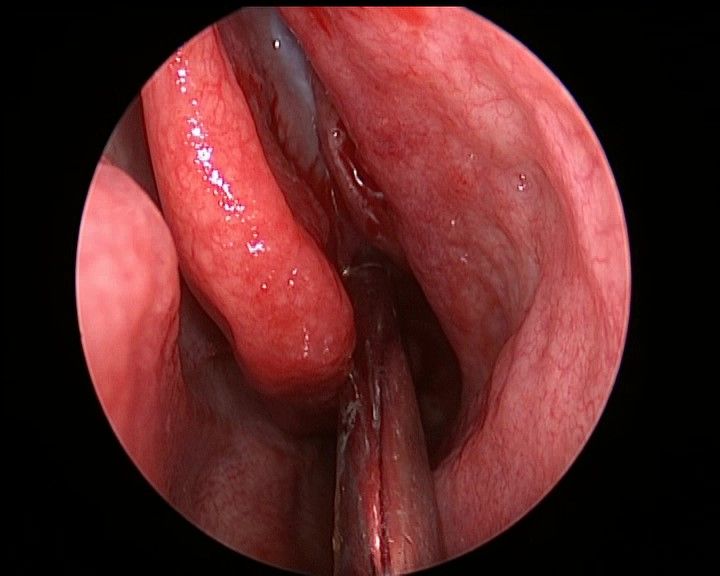

侧方观察右侧鼻腔侧壁结构

45度角观察右侧鼻腔侧壁

切除右侧中鼻甲后观察右鼻腔侧壁